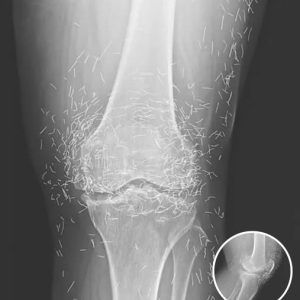

X-Ray Reveals Hundreds of Gold Needles in Woman’s Knees

A 65-year-old woman in South Korea discovered the surprising cause of her chronic knee pain: hundreds of tiny gold acupuncture needles embedded in her joints. She had…